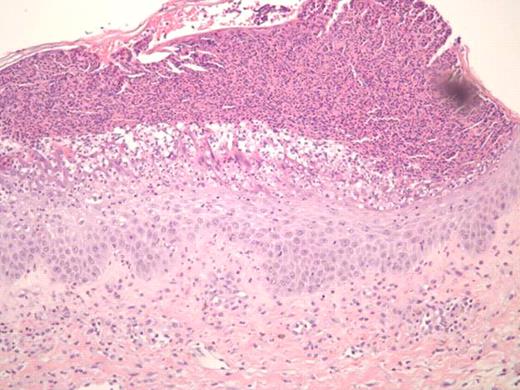

Treatment of sclerodermatous chronic graft versus host disease (cGVHD) remains a daunting challenge. Despite developments in prophylaxis for cGVHD, supportive care measures remain as the primary mode of therapy, with little evidence of treatments that reverse the process. Steroids and immunosuppressants are often ineffective, and extracorporeal photopheresis has been used with varying success. Recently, case reports have reported on the successful use of imatinib in treating sclerodermatous GVHD (Moreno-Romero et al, 2008; Leonardo Magro et al., 2009). We report a case of a 40-year-old male patient with extensive sclerodermatous cGVHD. In 2005 he underwent an unrelated stem cell transplant (SCT) for chronic myeloid leukemia. His transplant course was complicated by thrombotic thrombocytopenic purpura (TTP) associated with all standard immunosuppressive drugs (cyclosporine, tacrolimus and sirolimus). Two years later, the patient developed sclerodermatous GVHD and was given plaquenil, steroids, and photopheresis to manage this complication. Unfortunately, after months of treatment, he showed progressive disease, including increased contractures, and difficulties with inspiration. Based on case reports, and the patient's tolerance of imatinib prior to SCT, he was started on imatinib for his sclerodermatous GVHD. Within 5 days he developed generalized erythema, pustular rash, and skin sloughing (Figure 1). He was hospitalized for this severe reaction and was treated with high dose steroids after which, his symptoms began to improve. Resolution of erythema did not occur until months following initial exposure. Histological differential diagnosis included pustular psoariasis and Sneedon-Wilkinson syndrome. The skin biopsy revealed subcorneal pustular dermatosis (Figure 2). In view of this history, it is suggested that the exanthematous pustulosis was induced by imatinib in this patient. We recommend that close attention is paid to patients with cGHVD who are treated with imatinib and to intervene early in those who develop severe cutaneous reactions by stopping imatinib and starting appropriate therapy.

SEQ – Imatinib induced generalized erythema, pustular rash, and skin sloughing developed five days into treatment.